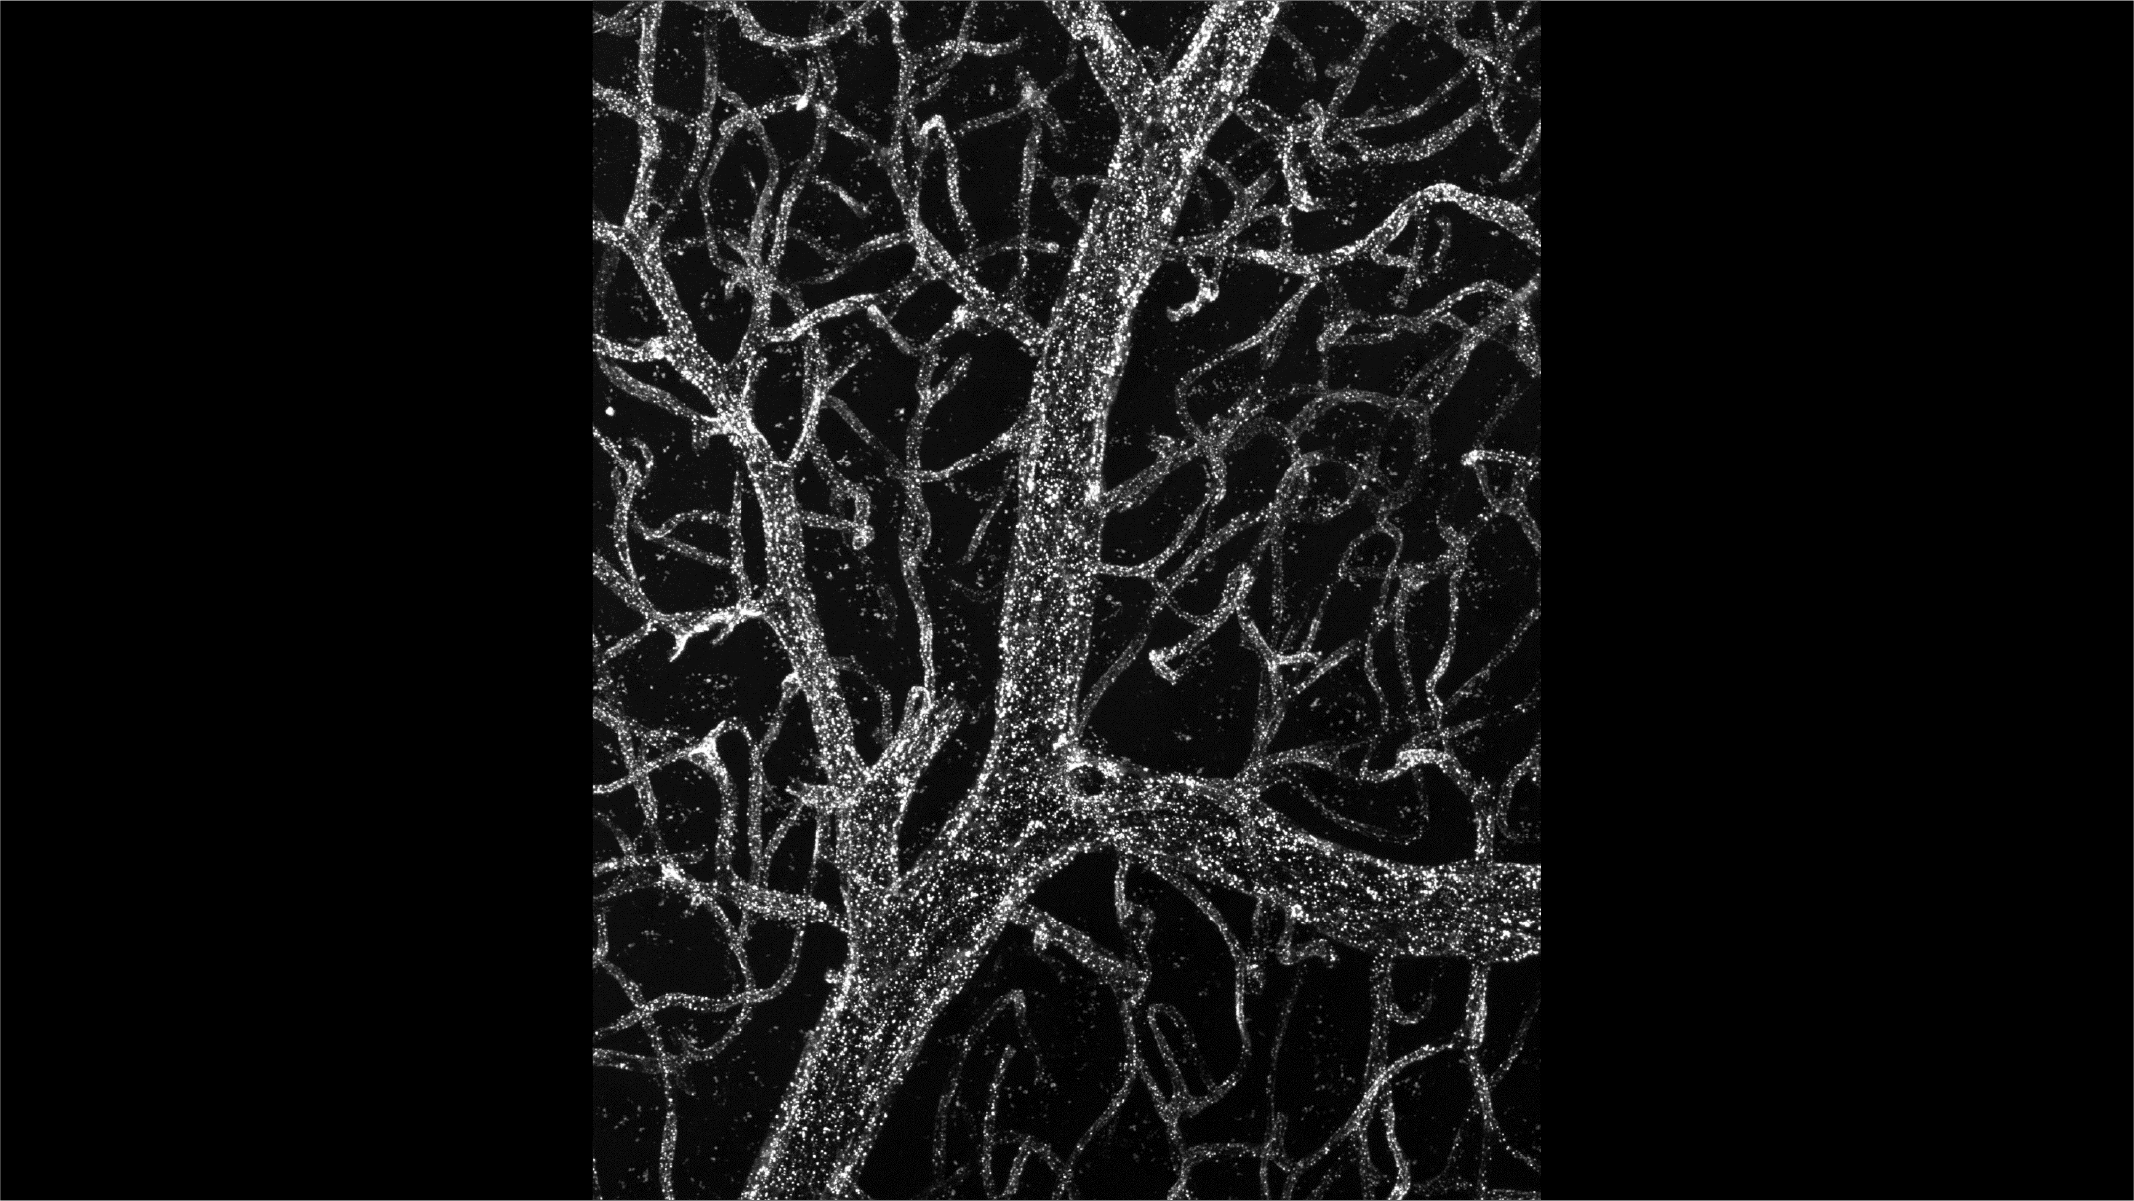

So the research team set out to get more of that picture. They added fluorescent labels to all the proteins in mouse plasma, the liquid part of the blood that doesn’t include all the blood cells, and then looked for the presence of these hundreds of different proteins in the mice’s brains.

They were expecting to see that some of those blood proteins made it to the brain, but they weren’t quite expecting the extent of it. Looking at where the delicate, branching blood vessels wrap around the brain, the team could see how much of the blood’s contents were exchanging with the brain at every point: “The brain was basically lit up like a Christmas tree,” Wyss-Coray said.

They also saw the labeled proteins inside every kind of brain cell they looked at – neurons, microglia, astrocytes. The plasma proteins weren’t just sloshing around between brain cells, but neurons and other brain cells actually seem to be absorbing blood proteins.